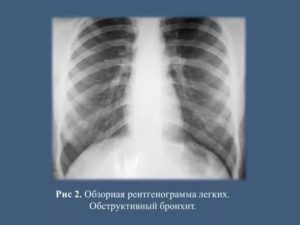

Обструктивный бронхит на снимке

Рентген грудной клетки позволяет обнаружить обструкцию. Это опасный симптом, который характеризует процесс закупорки дыхательных путей и нарушение вентиляции легких. При обструктивном бронхите картина снимка несколько меняется, все перечисленные признаки дополняются следующими характеристиками:

- заметно утолщение и смещение диафрагмы;

- сердце располагается вертикально, сто плохо влияет на главный орган;

- ткани легких становятся прозрачными и воздух не заметен;

- заметно ухудшение кровоснабжения, что и вызывает застой в легких;

- рисунок легких становится очаговым, в нижней доли заметно искривление;

- бронхи сильно уплотнены, структура нарушена;

- контуры сильно размыты, рисунок бронхиального дерева ярко выражен.

Признаки заболевания дополняются более опасными проявлениями. Обструктивный бронхит на рентгене выявляют по:

- увеличенной прозрачности и воздушности легких;

- признакам застоя крови в легочных тканях;

- смещению диафрагмы под действием воспаления;

- размытости структуры и расширению корня легкого.